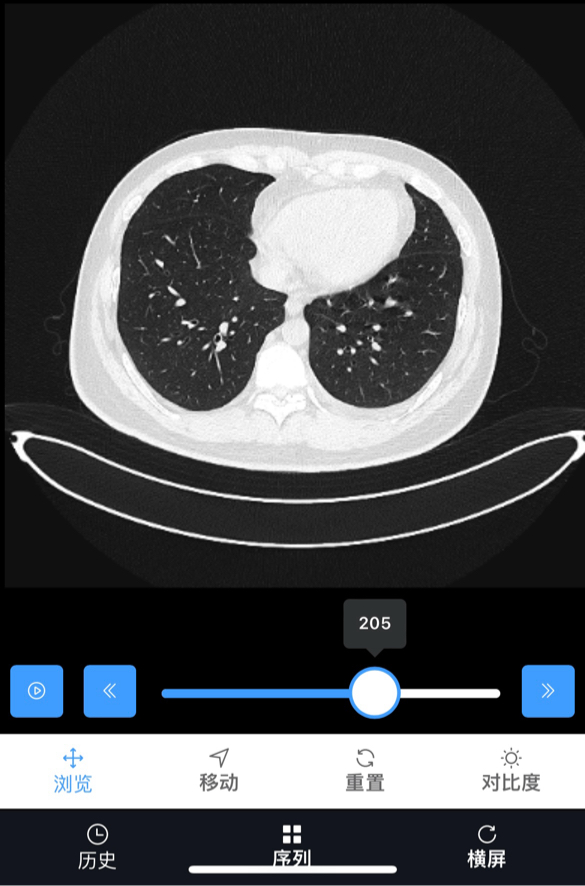

1.之前petct说病灶在腹膜后主动脉旁最大6.7,现在照ct是不是小了?

2.而且肺部白色点状是什么呀?目前有点感冒和痰。

ct里肿大淋巴结有没有变小,得请影像科或者血液科医生在电脑上量。